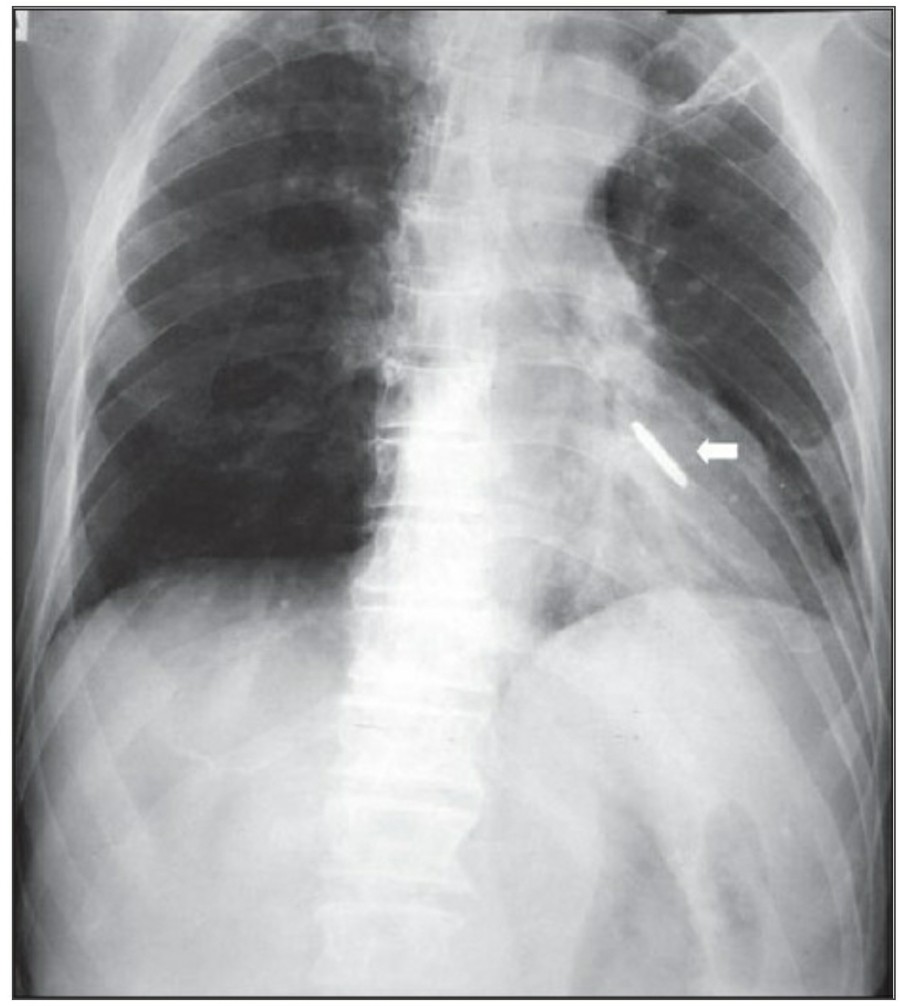

The thoracostomy tube

Supine AP radiograph에서 air는 anterior에, fluid는 중력에 의해 posterior에 위치하는 걸 인지하고 있어야 한다. Tube가 anterior에 위치하는지 아니면 posterior에 위치하는지는 단 한 장의 AP 사진으로 알기는 어렵다.

Pleural fissure 안에 위치하는 chest tube는 폐 표면이 늘어날 때 종종 배액이 안될 수 있으므로 적절히 기능을 하기 위해서 thoracic cavity 안에 거치되어야 한다. 마지막 side-hole은 radiopaque line의 interruption으로 확인할 수 있는데, 이 지점은 반드시 thoracic cavity 안에 위치해야 한다. Thoracic cavity 밖에 위치하거나 subcutaneous air가 확인되는 경우에 tube가 잘못 들어가 있음을 시사한다. Empyema에서 tube가 제대로 들어가 있지 않다면 배액이 잘 안 되거나 purulent fluid의 loculation이 발생하게 된다.